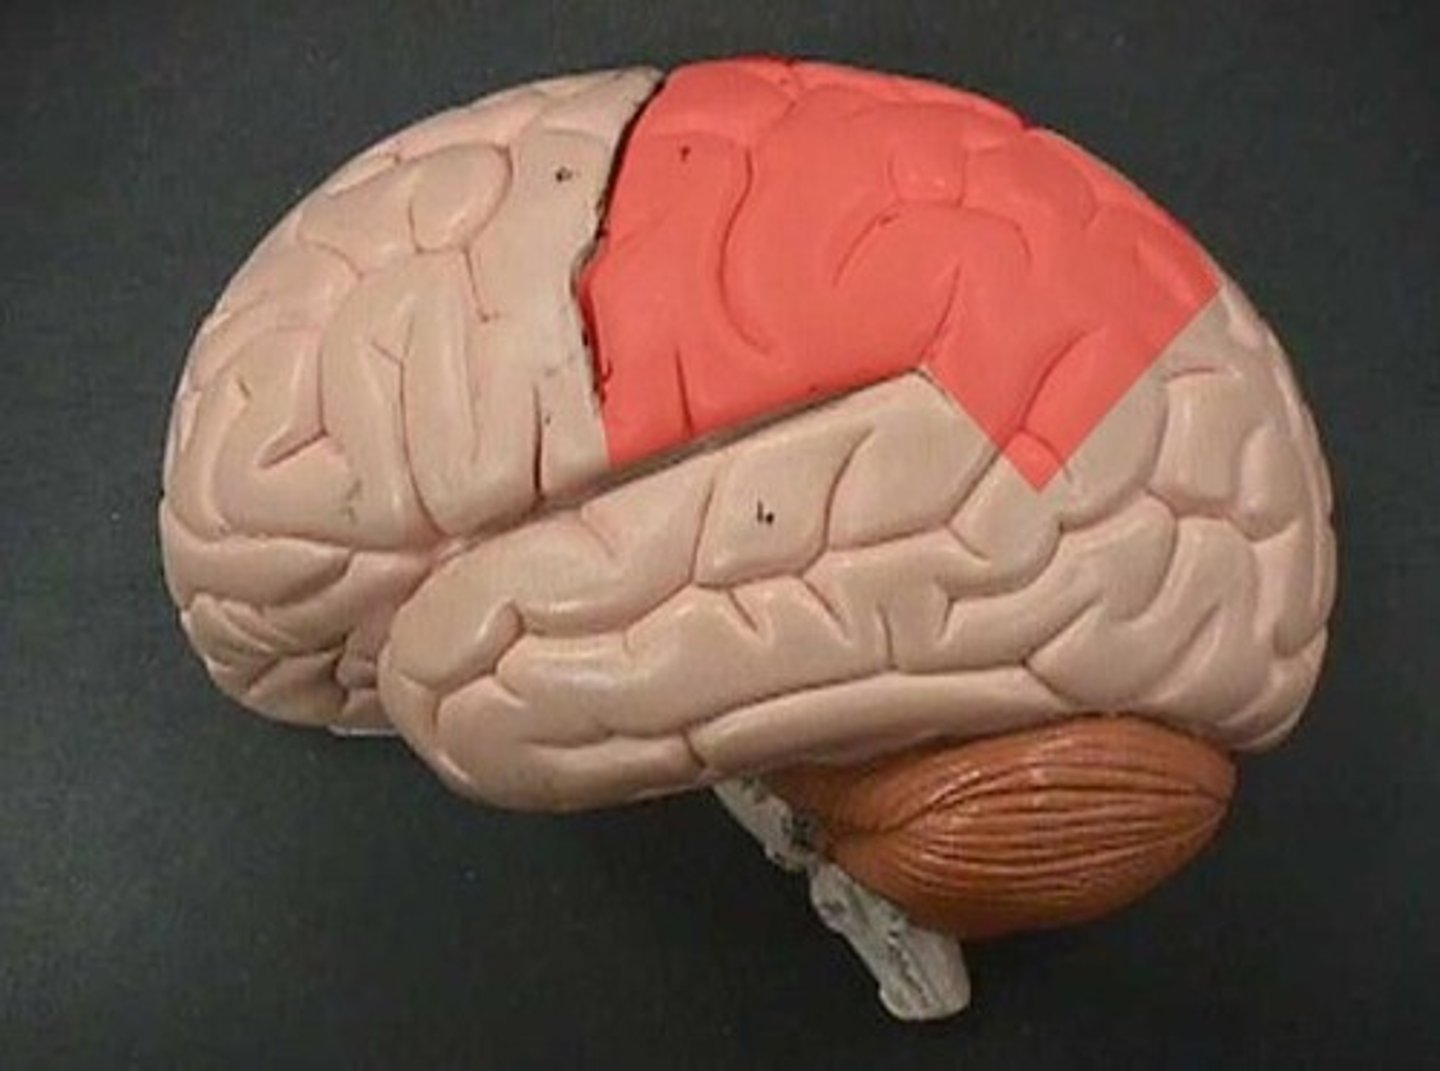

parietal lobe